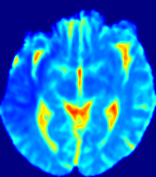

LesionRefer to captionRefer to captionRefer to captionRefer to captionRefer to captionRefer to caption𝐕rgbsubscript𝐕𝑟𝑔𝑏{\bf{V}}_{rgb}Refer to captionRefer to captionRefer to captionRefer to captionRefer to captionRefer to caption𝐕2subscriptnorm𝐕2{\|\bf{V}}\|_{2}Refer to captionRefer to captionRefer to captionRefer to captionRefer to captionRefer to captionRefer to caption3.53.53.52.82.82.82.12.12.11.41.41.40.70.70.70.00.00.0(mm/s)𝑚𝑚𝑠(mm/s)D𝐷DRefer to captionRefer to captionRefer to captionRefer to captionRefer to captionRefer to captionRefer to caption0.0200.0200.0200.0160.0160.0160.0120.0120.0120.0080.0080.0080.0040.0040.0040.0000.0000.000(mm2/s)𝑚superscript𝑚2𝑠(mm^{2}/s)Slice #1Slice #2Slice #3Slice #4Slice #5Slice #6

Figure 4: PIANO feature maps for another patient in the ISLES 2017 training set, where the lesion is located in the right hemisphere. Top row: segmented stroke lesion region (white) on different slices. The corresponding slices for the PIANO feature maps are shown in the following rows.

For a better insight into an estimated velocity field 𝐕𝐕{\bf{V}} and diffusion field 𝐃𝐃{\bf{D}}, we compute the following maps: (1) 𝐕rgbsubscript𝐕𝑟𝑔𝑏{\bf{V}}_{rgb}: Color-coded orientation map of 𝐕=(Vx,Vy,Vz)T𝐕superscriptsuperscript𝑉𝑥superscript𝑉𝑦superscript𝑉𝑧𝑇{\bf{V}}=(V^{x},V^{y},V^{z})^{T}, obtained by normalizing 𝐕𝐕{\bf{V}} to unit length and mapping its 3 components to red, green, blue respectively; (2) 𝐕2subscriptnorm𝐕2\|{\bf{V}}\|_{2}: 222 norm of 𝐕𝐕{\bf{V}}; (3) D𝐷D: scalar field in Eq. 5.

Fig. 3 and Fig. 4 show the PIANO feature maps estimated from two ISLES 2017 patients: all are highly consistent with the lesion in both cases. Details of the blood flow trajectories are revealed in 𝐕rgbsubscript𝐕𝑟𝑔𝑏{\bf{V}}_{rgb} by the ridged patterns and the sharp changes of colors in the unaffected (right) hemisphere, while the flat patterns appearing within the lesion provide little directional information about the velocity and indicate low velocity magnitudes. Velocity magnitudes are more directly visualized via 𝐕2subscriptnorm𝐕2\|{\bf{V}}\|_{2}, from which one can easily locate the lesion where 𝐕2subscriptnorm𝐕2\|{\bf{V}}\|_{2} is low. D𝐷D also indicates lower diffusion values in the lesion, though with less contrast potentially due to the fact that it captures the accumulated effect of CA diffusion at the voxel-level.